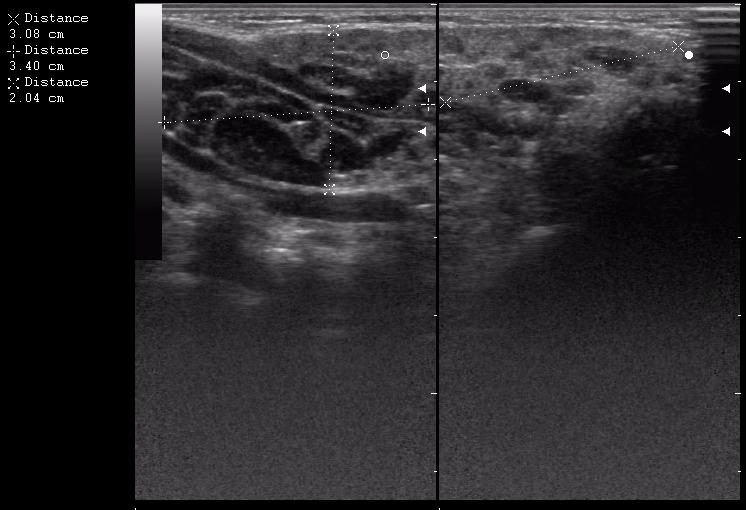

интранодулярные лимфоузлы в околоушной железе

иногда я меряю так, и немножко ошибаюсь)

размер железы 30,8 + 34 = 64,8 мм х 20,4 мм